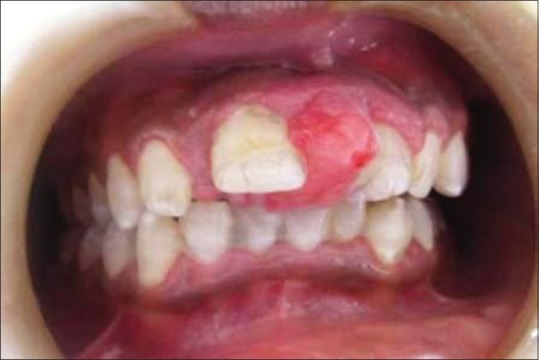

Out of the 5 GCG lesions identified [Table 1], 2 peripheral lesions were located in the maxillary anterior region. Three central lesions were, with 2 situated in the mandibular anterior region and 1 in the posterior region. Two of the central lesions crossed the midline. The size of the peripheral lesions was relatively small, varying from 1.0 cm × 1.0 cm to 2.0 cm × 1.5 cm while the central lesions varied in size from 2.0 cm × 2.5 cm to larger 5.0 cm × 4.0 cm lesions. The peripheral lesions were asymptomatic, soft, rubbery, and purplish red in color with one case showing calculus deposits on the adjacent teeth [Figure 3]. The central lesions were bluish red in color, hard with slight pain, or asymptomatic [Figure 4]. Radiographically, all the GCG identified lesions had a radiolucent cystic appearance, with variable levels of margin definition.

| Figure 3:Preoperative photograph showing peripheral giant cell granuloma lesion in relation to teeth number #11 and 21[37]

| Figure 4:Preoperative photograph showing central giant cell granuloma lesion in relation to teeth numbers #33–42